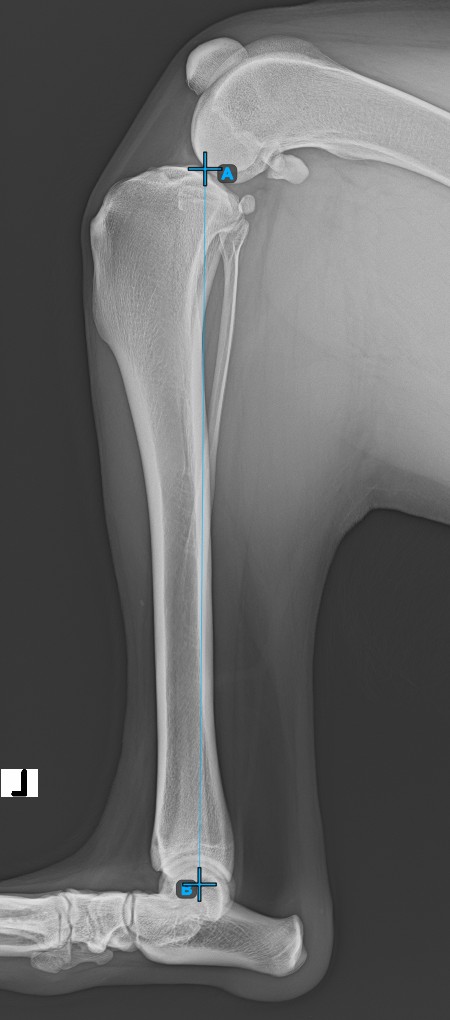

The TPA Angle (Tibial Plateau Angle) is one of the most important orthopedic measurements in veterinary medicine, measuring the slope of the tibial plateau relative to the long axis of the tibia. Select the TPA Angle measurement from the Advanced Measurement menu and assign the left mouse button to it.

Start the measurement by marking the Eminentia Intercondylaris, which is located on the joint connecting the femur and the tibia.

Continue by marking the midpoint of the Cochlea, located at the end of the tibial bone. The line created between the Eminentia Intercondylaris and the midpoint of the Cochlea represents the long axis of the tibia.

The image below depicts the usual placement of the midpoint of the Cochlea.

../../_images/image233.jpg